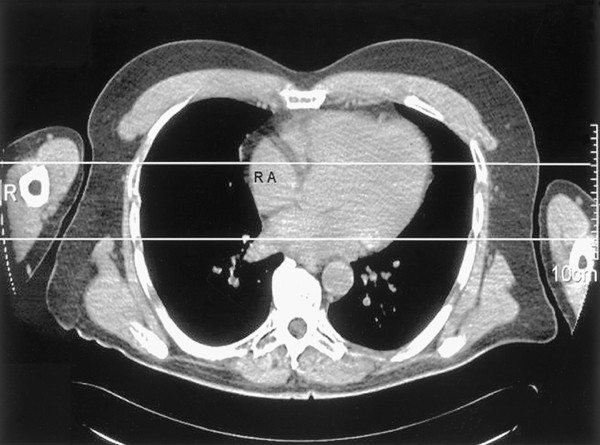

In all, 25 subjects (16 hypertensive patients, 11 males, mean historic period 52.9±16. 5 (s.d.) years, BMI 26.1±4.9 (south.d.) kg/m2, arm circumference correct 29.5±0.7 (south.d.) cm and left 29.3±one.two (due south.d.) cm) participated in the report. Pregnant women, patients with BP differences between the ii arms larger than 10 mmHg and patients with arm circumferences larger than 35 cm were excluded. The BP measurements were performed using ii automatic oscillometric devices (Bosomat; Boso oscillomat, Bosch, Jungingen, Frg; float size 28 × 12.5 cm). All BP readings were taken simultaneously at both arms, with the subject comfortably supine on an examination bed with 1 small absorber nether the head. To examination for BP differences between the 2 arms, i BP reading was get-go performed with the patients in the described supine position and both arms placed on the bed, with the palms upward. One arm (at random right or left) was then supported with a specially designed pillow with the cubital fossa and upper arm at half-distance between the bed and the sternum (approximation of the right atrium level), whereas the other arm remained on the bed (Figure 1). Later on 5 min of remainder, iii BP and HR were measured, 1 min apart. The arm position was switched thereafter, with the arm offset supported on the pillow now being placed on the bed and vice versa. Again after 5 min of rest, the three BP and 60 minutes readings were repeated.

Computerised tomography illustrating the difference between the arm levels used in the present study (right arm supported at the right atrium level and left arm supported on the exam bed). R: correct arm; 50: left arm; RA: correct atrium.